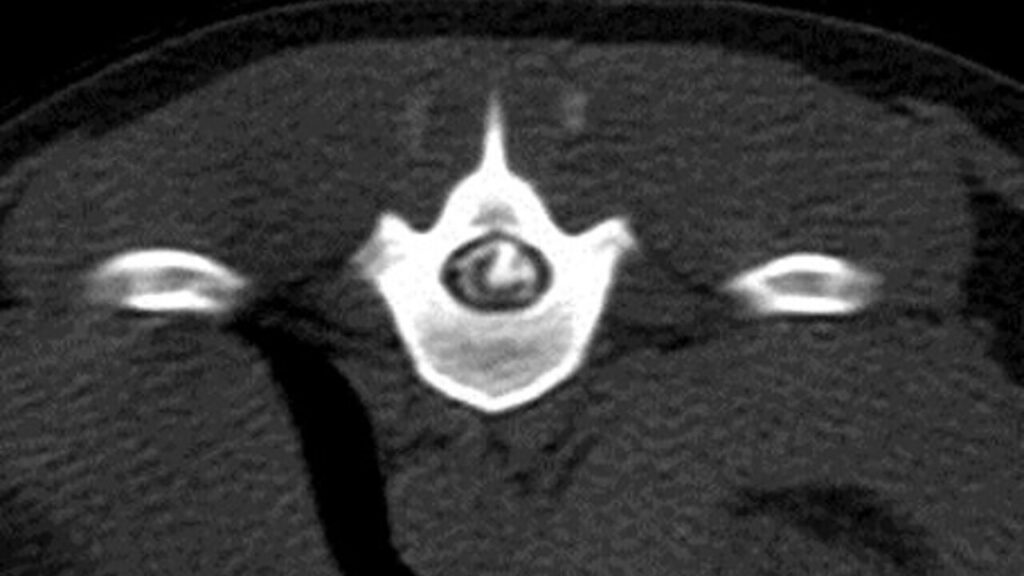

- En el mielo-TAC, en la reconstrucción sagital, se observó un trayecto lineal de contraste en dirección ventrodorsal desde el espacio intervertebral T12-T13 hasta el aspecto dorsal del parénquima medular a nivel de T12.

- Además, se observó acúmulo de contraste intramedular a ese mismo nivel con cierta atenuación de la línea ventral de contraste (imágenes 2A y 2B).

Imagen 2. Caso 1. A) Reconstrucción sagital en ventana de hueso del mielo-TAC en la que se observa el trayecto de contraste en dirección ventrodorsal desde el espacio T12-T13 hasta el aspecto dorsal del parénquima medular a nivel de T12. Se aprecia estrechamiento del espacio T12-T13 y atenuación del contraste ventralmente a ese mismo nivel. B) Imagen transversal del mielo-TAC, adquirida en algoritmo de hueso a nivel de T12 del mielo-TAC, en la que se puede ver el acúmulo de contraste intramedular y su trayecto.